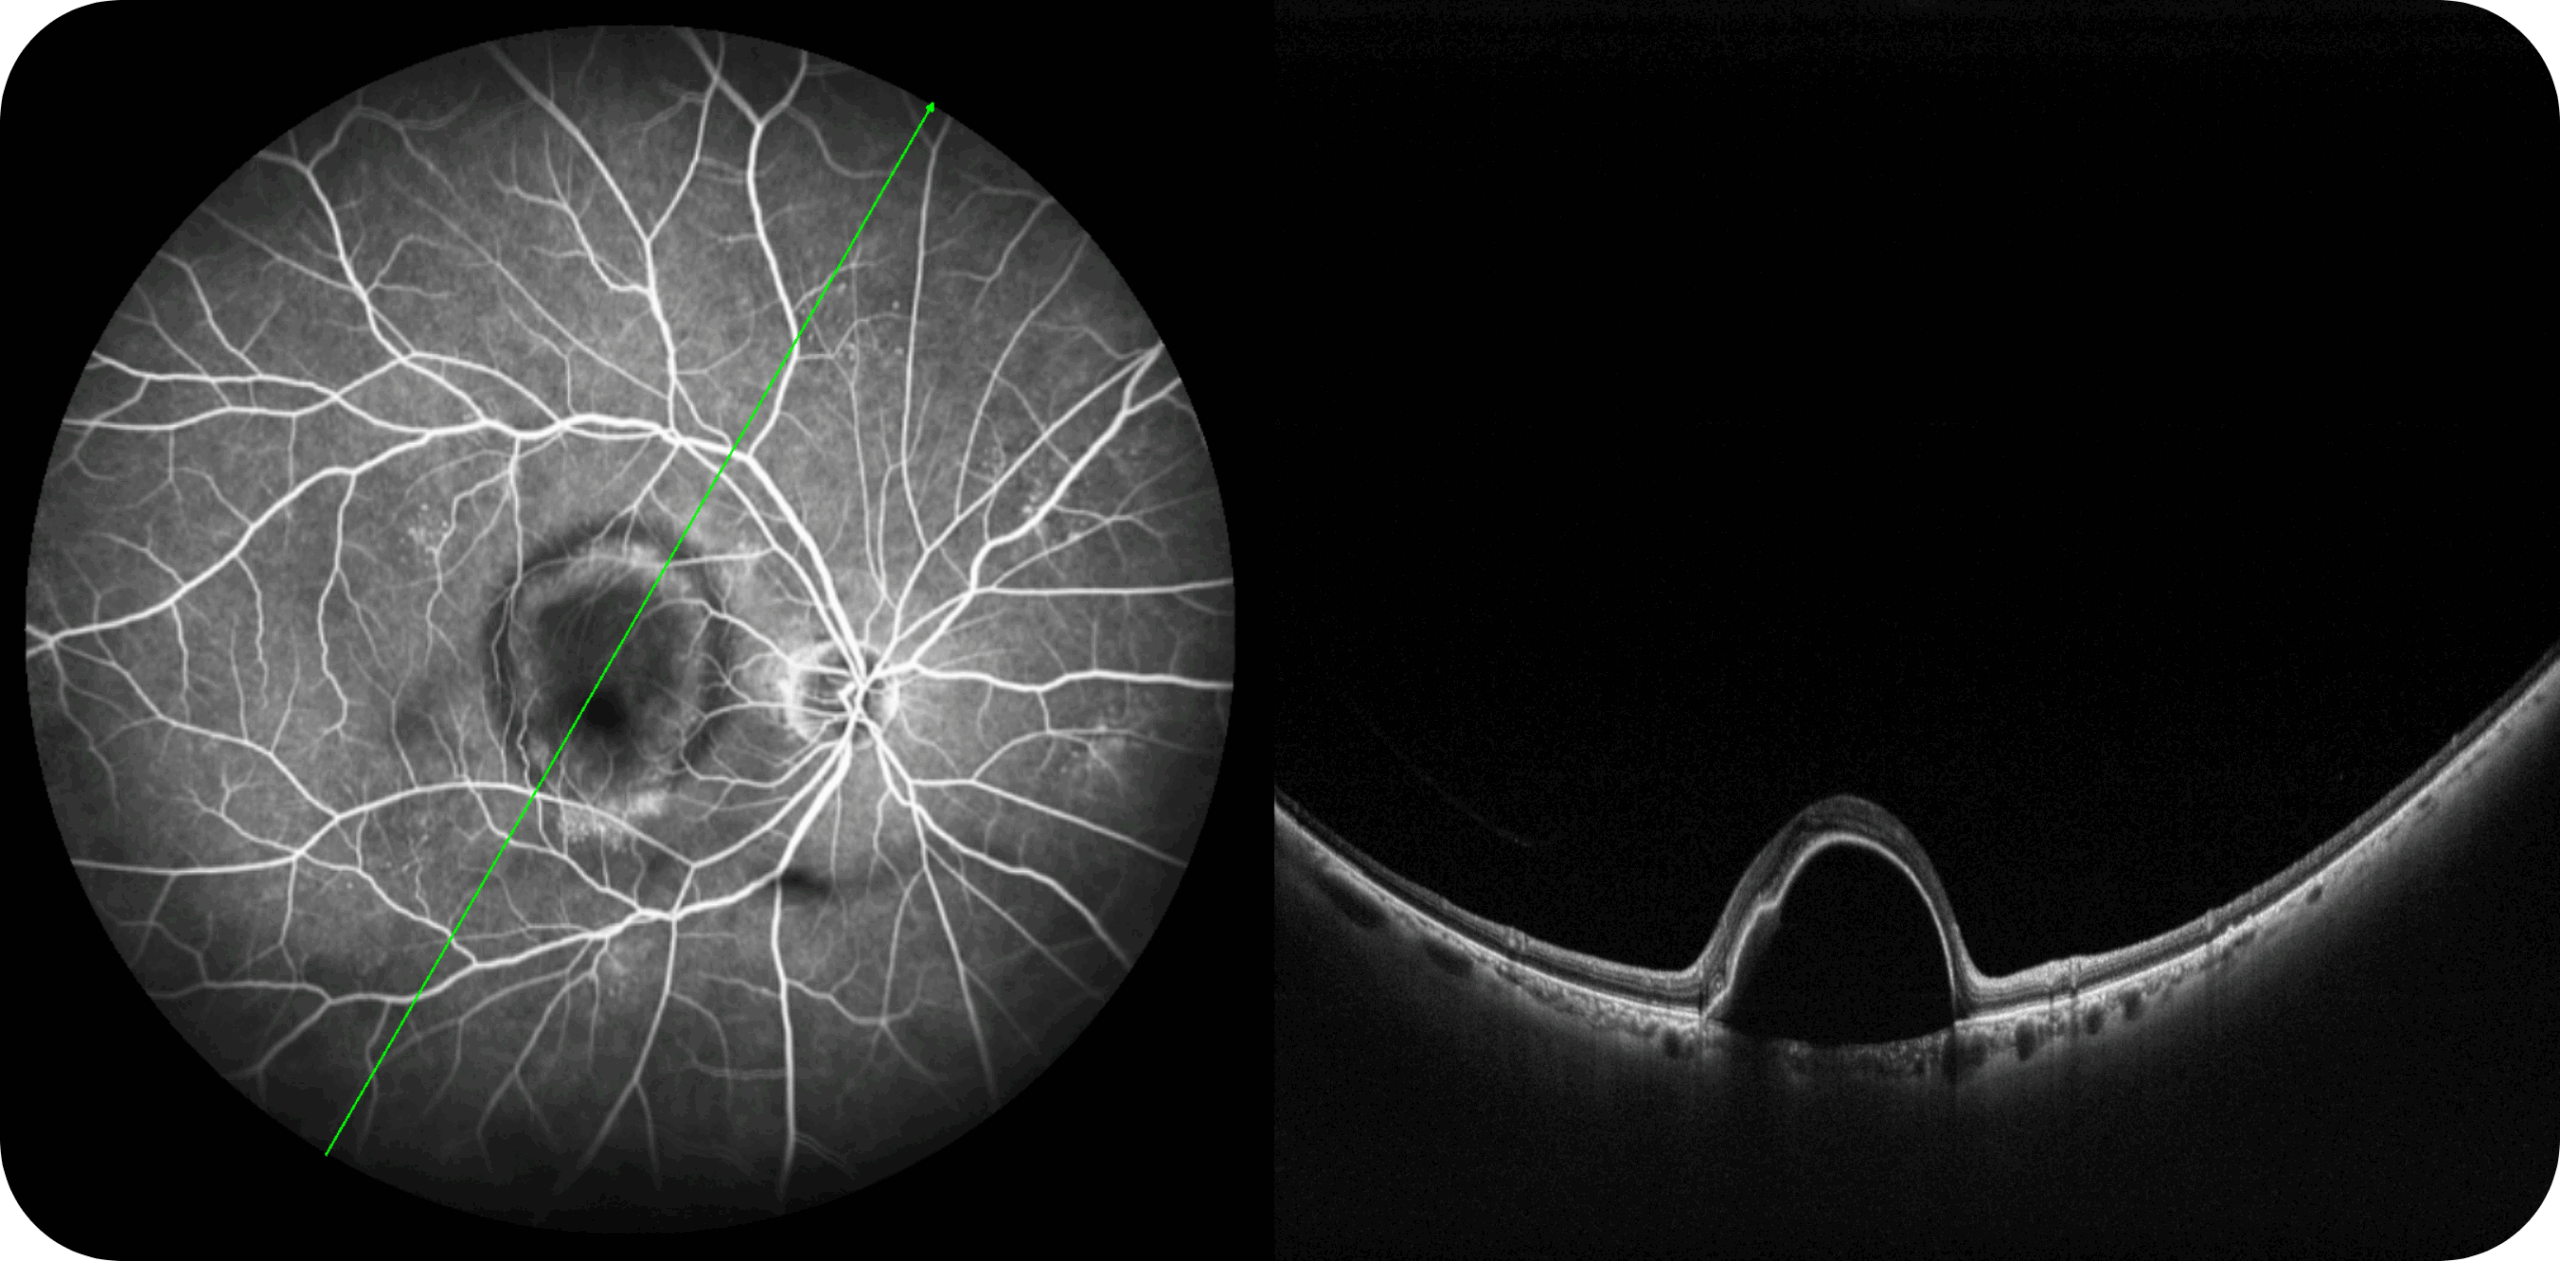

Uma única varredura pode obter rapidamente imagens sincronizadas de imagens coloridas de campo ultralargo/FAF/FFA/ICGA e SS-OCT, alcançando sincronização em tempo real e alinhamento preciso de imagens planas e estruturais da retina, melhorando significativamente a eficiência da inspeção e otimizando o processo de diagnóstico e tratamento.” Uma única varredura pode obter rapidamente imagens sincronizadas de imagens coloridas de campo ultralargo/FAF/FFA/ICGA e SS-OCT, alcançando sincronização em tempo real e alinhamento preciso de imagens planas e estruturais da retina, melhorando significativamente a eficiência da inspeção e otimizando o processo de diagnóstico e tratamento.

Multi-Modalidade

Altamente integrado com tecnologias como SLO confocal e SS-OCT, ele combina imagens coloridas SLO de campo ultralargo, angiografia confocal a laser, autofluorescência e imagens tomográficas de segmento anterior e posterior ultraamplas e profundas em um único sistema.

Exames de segmento anterior com OCT de 28mm.

Angiografia multimodal (FA e ICG – disponível nas versões avançadas).

OCTA até 220° em mosaico, para análise detalhada da vascularização.